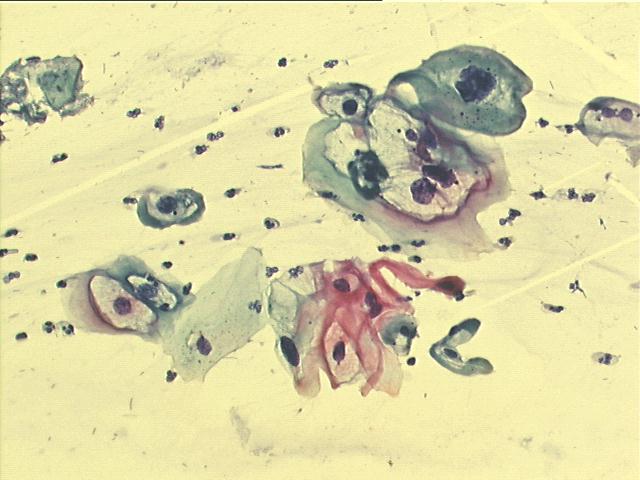

Routine Pap smear (exo- and endo-cervix) of 20-year old female

500x Papanicolaou staining